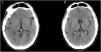

This is the case of a 47-yearl old man with a past medical history of native mitral aortic valve acute endocarditis who required valvular repair and supracoronary tube implantation. The patient is admitted to the ICU after a scheduled reintervention due to severe paravalvular leak followed by valvular replacement with mechanical prosthesis. Initially extubated and without neurologic focality. A few minutes after experiencing the early seizure the patient requires orotracheal intubation. The emergency cranial CT scan performed (Fig. 1) reveals the presence of air into the right middle cerebral artery territory, M2 (blue arrow [the color of the figure can only be seen on the electronic version]) and part of its cortical branches, as well as air bubbles into the left posterior cerebral artery (x) that consistent with gas embolism. The radiographic follow-up performed 48 h later (Fig. 2) reveals the presence of an extensive established right parietal-temporal-occipital and left occipital ischemic infarction with slight midline deviation.